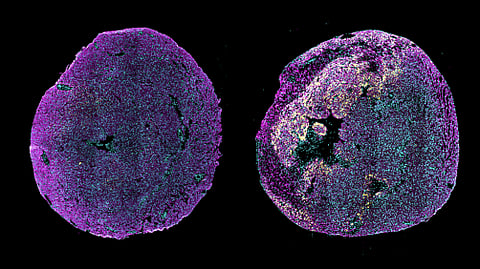

Immunofluorescence image of transverse heart sections from a healthy neonatal mouse